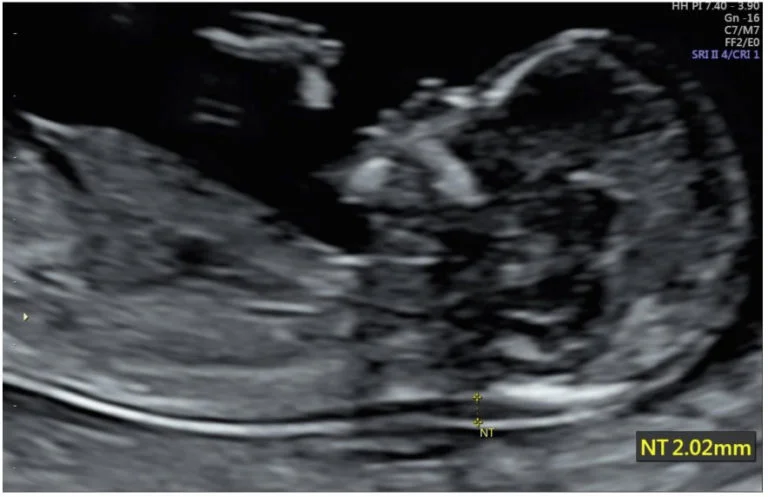

One of the first structured screenings offered during this time is the nuchal translucency scan, usually done between 11 and 14 weeks.

Nuchal translucency refers to a thin layer of fluid that naturally collects at the back of the baby’s neck. Every fetus has this. It is not abnormal on its own.

What matters is the thickness of this fluid space.

When and How the Measurement Is Done

The scan is performed when the baby’s crown-rump length falls within a specific range.

This typically corresponds to 11 weeks to 13 weeks and 6 days.

During the scan:

- The baby must be in a neutral position

- The neck should not be overly flexed or extended

- The measurement is taken at the widest visible point of the fluid

What Is Considered Normal?

There is no single number that applies to all pregnancies. The measurement is interpreted relative to gestational age.

In general:

- Around 1.0 to 2.5 mm is commonly seen in low-risk cases

- Values above 3.5 mm are usually considered elevated